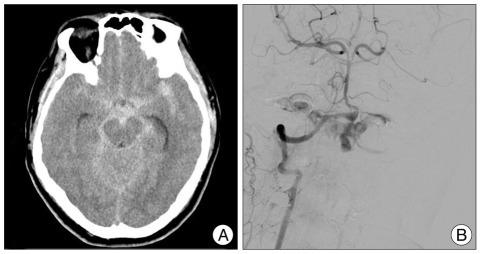

We report an unusual case of lateral medullary infarction after successful embolization of the vertebral artery dissecting aneurysm (VADA). A 49-year-old man who had no noteworthy previous medical history was admitted to our hospital with a severe headache. Computed tomography (CT) revealed a subarachnoid hemorrhage, located in the basal cistern and posterior fossa. Cerebral angiography showed a VADA, that did not involve the origin of the posterior inferior cerebellar artery (PICA). We treated this aneurysm via endovascular trapping of the vertebral artery distal to the PICA. After operation, CT revealed post-hemorrhagic hydrocephalus, which we resolved with a permanent ventriculoperitoneal shunt procedure. Postoperatively, the patient experienced transient mild hoarsness and dysphagia. Magnetic resonance image (MRI) showed a small infarction in the right side of the medulla. The patient recovered well, though he still had some residual symptom of dysphagia at discharge. Such an event is uncommon but can be a major clinical concern. Further investigation to reveal risk factors and/or causative mechanisms for the medullary infarction after successful endovascular trapping of the VADA are sorely needed, to minimize such a complication.

我们报告了一例在成功栓塞椎动脉夹层动脉瘤(VADA)后发生外侧延髓梗死的罕见病例。一名既往无显著病史的49岁男性因严重头痛入院。计算机断层扫描(CT)显示蛛网膜下腔出血,位于脑基底池和后颅窝。脑血管造影显示一个不涉及小脑后下动脉(PICA)起源的VADA。我们通过对PICA远端的椎动脉进行血管内圈套术治疗该动脉瘤。术后,CT显示出血后脑积水,我们通过永久性脑室腹腔分流术解决了这一问题。术后,患者出现短暂的轻度声音嘶哑和吞咽困难。磁共振成像(MRI)显示延髓右侧有一个小梗死灶。患者恢复良好,尽管出院时仍有一些吞咽困难的残留症状。这样的事件并不常见,但可能是一个主要的临床问题。迫切需要进一步研究以揭示成功进行VADA血管内圈套术后延髓梗死的危险因素和/或致病机制,以尽量减少这种并发症。